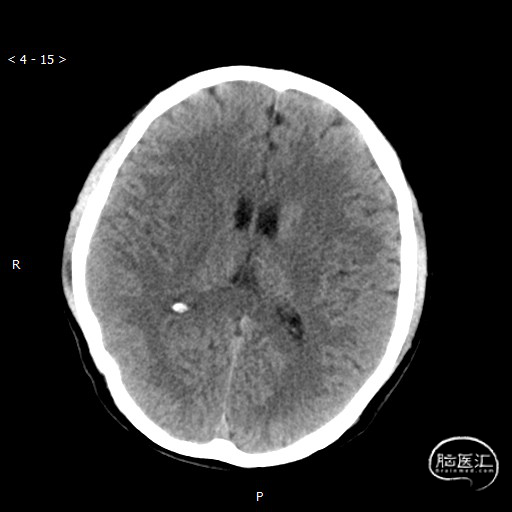

头颅CT(2020-05-05)术后即刻:

右侧尾状核头、右侧豆状核区见片团高密度影,CT值约50Hu。右侧基底节区见片状低密度影,CT值约27Hu。大脑纵裂、小脑天幕密度增高。中线结构居中。

右侧基底节区脑梗死;右侧尾状核头、右侧豆状核区高密度影,脑出血?对比剂?建议复查;大脑纵裂、小脑天幕密度增高,考虑对比剂影。